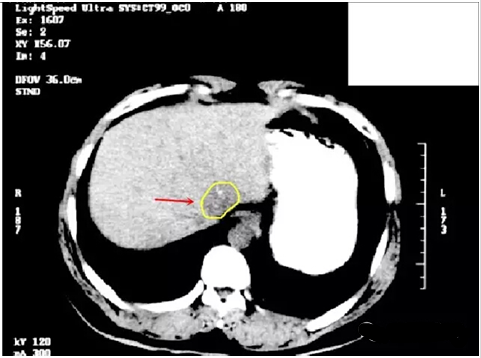

肝癌病例:大小為3cm的肝癌

下圖分別為質(zhì)子治療的10% 50% 70% 95%的劑量分布情況,對(duì)正常的肝臟組織的有效保護(hù),充分顯示了質(zhì)子治療的劑量學(xué)優(yōu)勢(shì)。